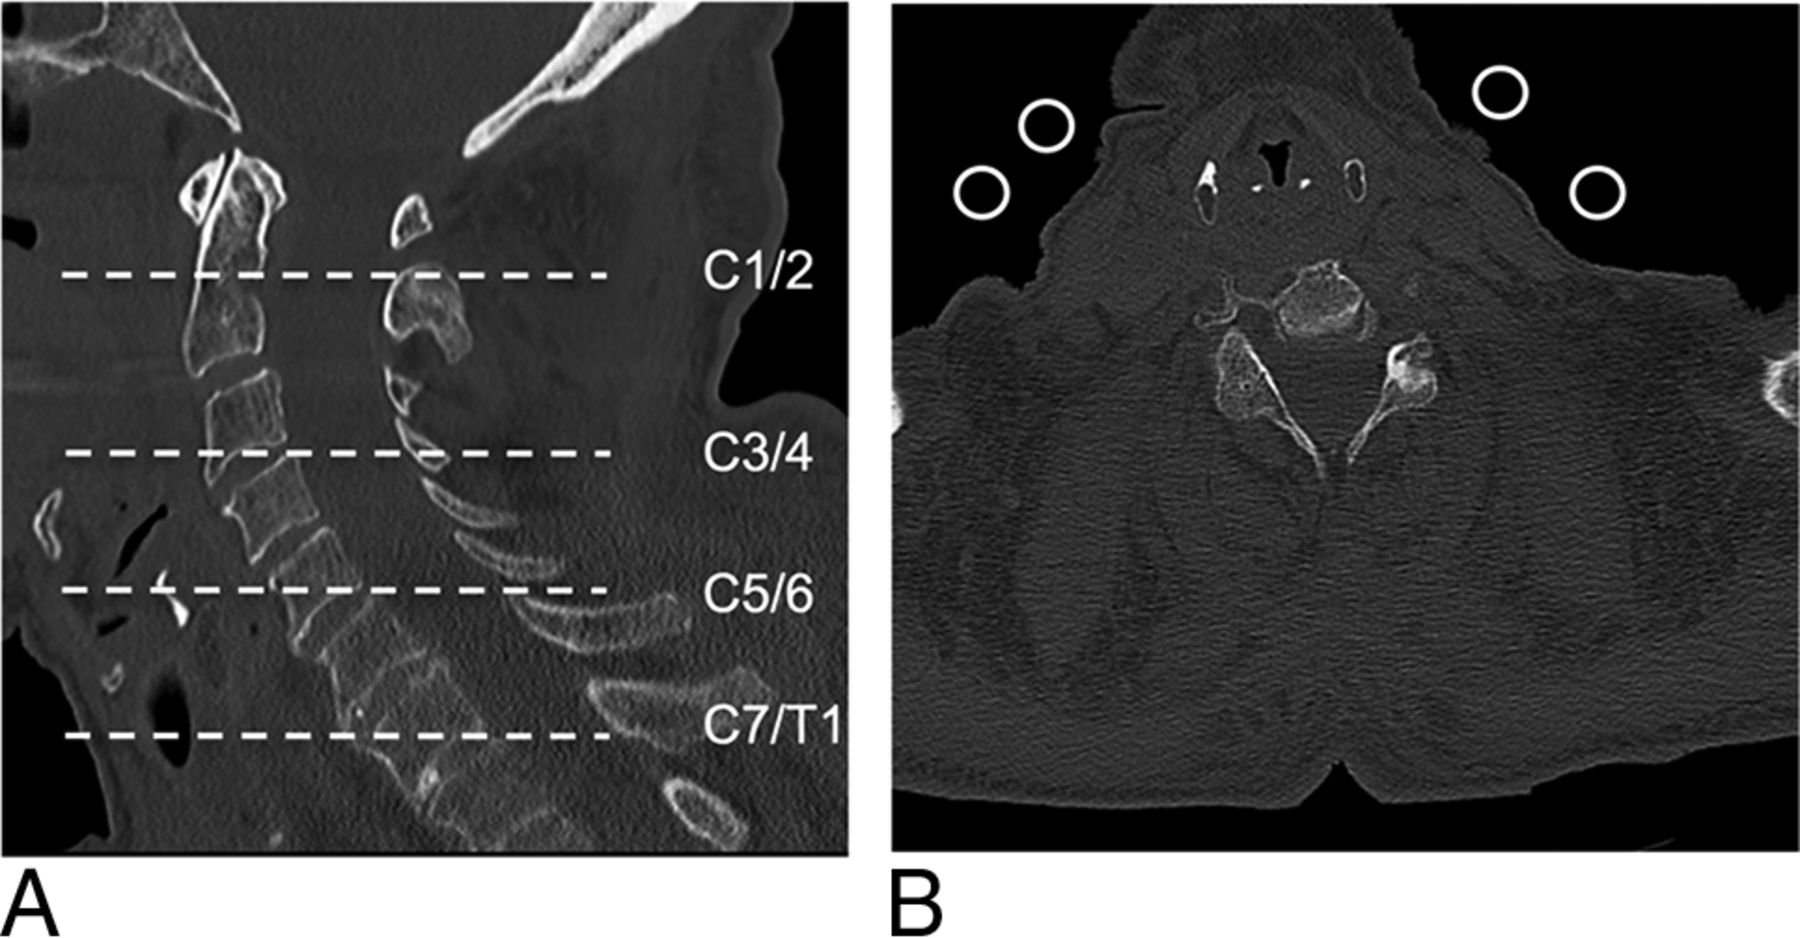

Images were reconstructed using both a conventional FBP and an IR (sinogram-affirmed iterative reconstruction, strength 3) algorithm as described elsewhere in bone convolution kernels (B70 hours for FBP and I70 hours for IR algorithms, respectively).7⇓–9 We used the following image reconstruction parameters: FOV, 15 × 15 cm to 21 × 21 cm according to the specimen constitution; section thickness/increment, 0.75/ 0.75 mm. Lateral body width was measured on anteroposterior topograms at 3 different heights: C3, C5, and C7 (Fig 1). Shoulder level was defined as the level of the cervical spine, on which the bony shoulder girdle is superimposed on the lateral topogram (Fig 1). For comparison of the height of the shoulder girdle in a clinical setting, topograms of cervical spine CTs of 30 nonintubated patients (15 women, 15 men; mean age, 66.9 ± 22.7 years) at the emergency department in 1 week were reviewed by 1 reader. The height of the shoulder girdle was assessed on the lateral topogram and recorded.

Lateral body width was measured on each anteroposterior topogram of the cadaveric specimens at 3 different heights: C3, C5, and C7 (A). On the lateral topogram, the shoulder level of this cadaveric specimen was C5 (B).